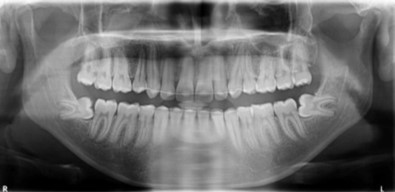

Cephalometric analysis revealed a skeletal Class II pattern, with an orthognathic maxilla and retrognathic mandible with high mandibular plane angle and severely proclined maxillary and mandibular incisors with increased lower anterior facial height. (Figure 3).

Post treatment lateral cephalometric radiograph was taken to assess the treatment changes. (Figure 9). The changes in maxilla in the anteroposterior direction was insignificant, however an increase in the length of the mandible measured from Condylion (Co) to Gnathion (Gn) and an increase in anterior facial height was observed. Maxillary incisors were retracted dramatically by 8mm and the mandibular incisors were proclined by 3mm to camouflage the skeletal class II malocclusion.(Table 1). Effective expansion of the maxillary constriction as an end-of treatment goal was achieved. (Figure 10a,Figure 10b).

| Variable | Norm | Pre-treatment | Post-treatment |

| SNA (degrees) | 82 ± 2 | 80 | 80 |

| SNB (degrees) | 80 ± 2 | 72.5 | 71 |

| ANB | 2 ± 2 | 7.5 | 9 |

| U1 to NA (degrees) | 22 | 26 | 17 |

| U1 to NA (mm) | 4 | 9 | 1 |

| L1 to NB (degrees) | 25 | 30 | 33 |

| L1 to NB (mm) | 4 | 8 | 11 |

| N-Me (mm) | 123 ± 5 | 112 | 142 |

| N-ANS (mm) | 56 ± 3 | 53 | 66 |

| ANS-Me (mm) | 70 ± 3 | 59 | 78 |

| FMA (degrees) | 25 | 32 | 36 |

| Co-Gn (mm) | - | 102 | 121 |

| E-plane LL (mm) | -2 ± 2 | 2.5 | 5 |